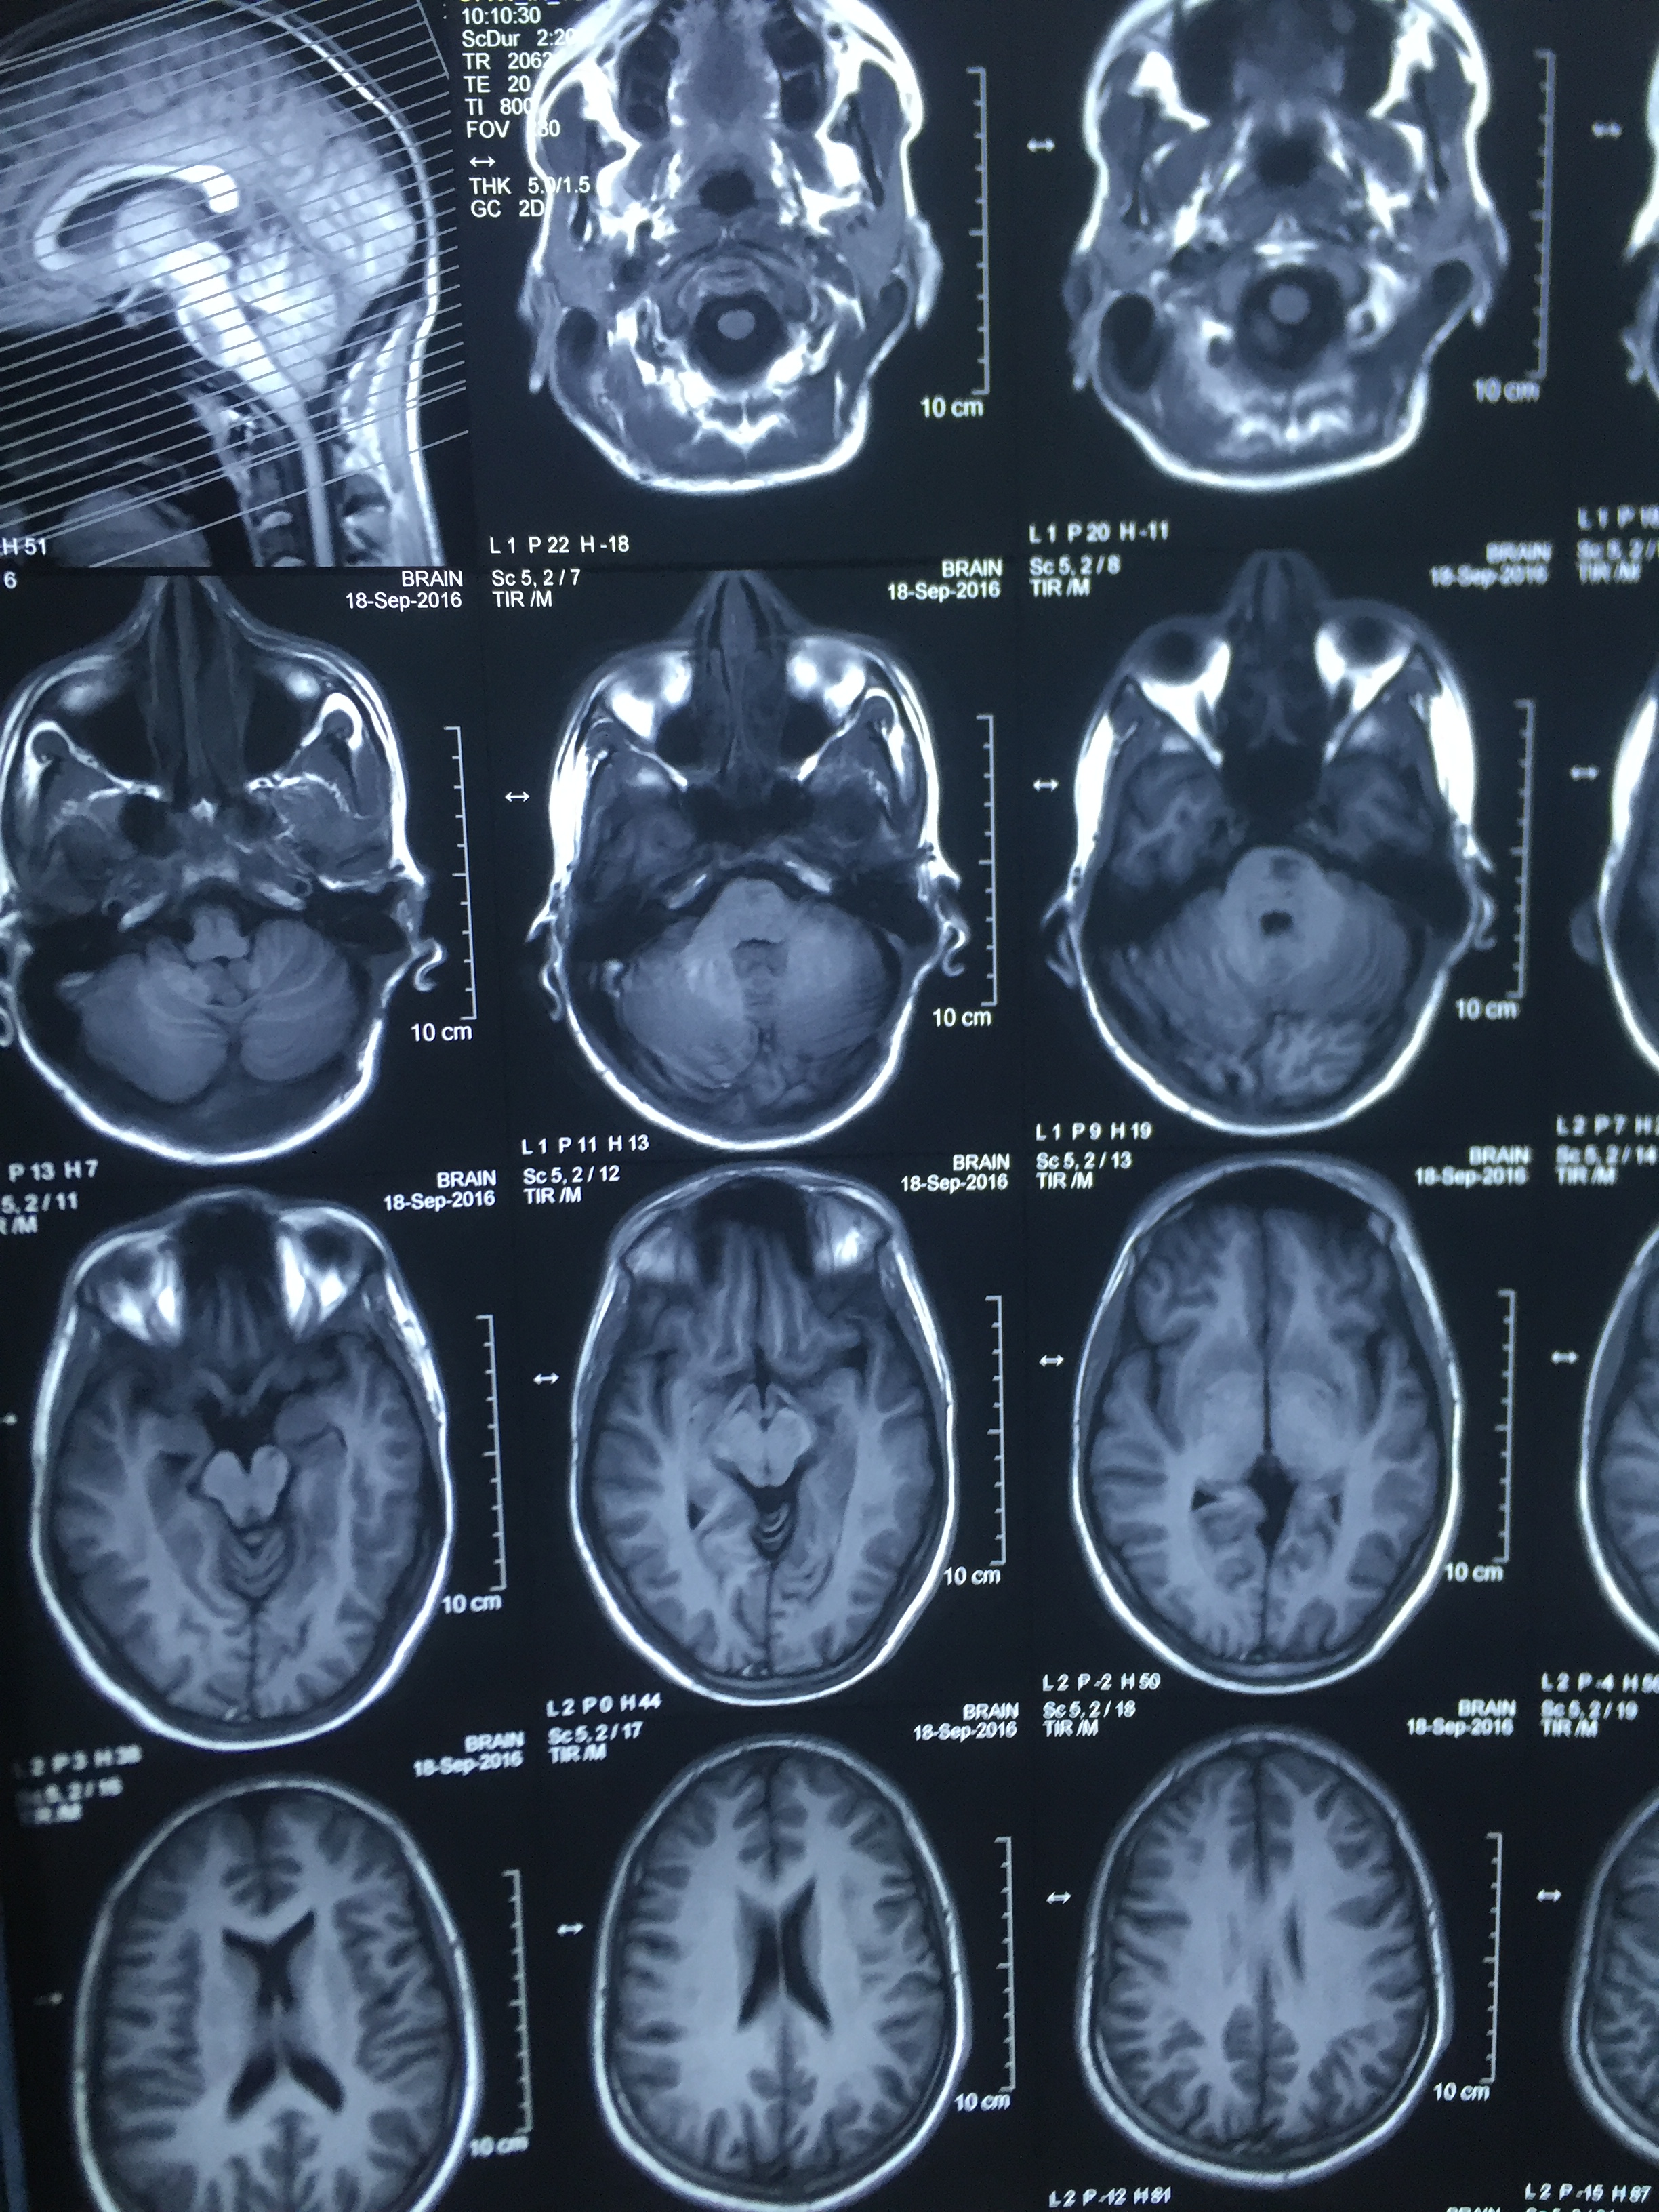

Brainstem Cavernoma : Surgery - Microsurgical excision of cavernoma